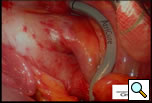

The patient is positioned with the right side up and is prepped and draped so as to have access to the lateral chest and the midline. A 10mm 30 degree thoracoscope is introduced into the right chest in the 6th or 7th interspace in the anterior axillary line at the level of the xiphoid (Right Side MiniMAZE), and the pericardium and pulmonary hilum are examined. A 6cm non-rib spreading access incision is made in the 3rd intercostal space and a soft tissue retractor inserted (Cardiovations, Sommerville, NJ). The overlying pericardial fat may be excised as necessary with appropriate attention to the phrenic nerve. The pericardium is opened anteriorly and parallel to the right phrenic nerve. Once the pericardium is opened, stay sutures are placed to maximize exposure (Figure 1). High frequency stimulation is then performed to identify and map vagal ganglionic plexi around the PVs and Waterson’s groove [2]. Pulmonary vein electrocardiograms (ECG) and corresponding surface ECGs are documented (Figure 2). Patients in sinus rhythm are then paced by placing the electrode on the pulmonary veins. Following EP mapping, blunt dissection is performed to open the oblique sinus between the right inferior pulmonary vein and the inferior vena cava.